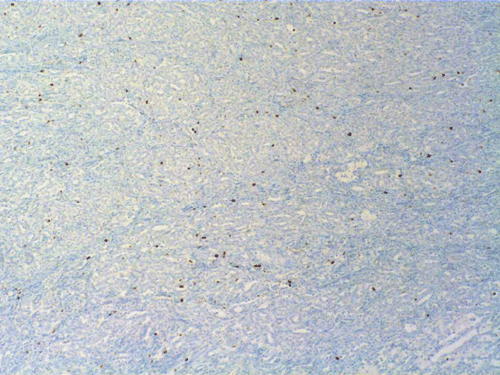

N. Ki67 |

Two major patterns are revealed. In the first pattern, the tumor cells grow in a densely packed tubular pattern with mucinous content (Panel A and B). In some other areas, the tubular pattern is replaced by interlacing fascicles of spindle cells separated by mucinous pools (Panel C and D). In some areas, the spindle cells are solidly packed (Panel E). In both areas, the nuclear are bland in appearance and without significant mitotic acivity. The tumor cells, both in the spindle cell area and tubular areas are strongly positive for cytokerain AE1/AE3, cytokeratin 7, Cam5.2, and epithelial membrane antigen (EMA) respectively (Panel F, G, H and I). The tumor cells are also negative for synaptophysin (Panel J and K) and CD10 (Panel L and M). The positive cells in Panel M are residual non-neoplastic renal tubules. The Ki67 labeling (Panel N) is low (about 1-2%).